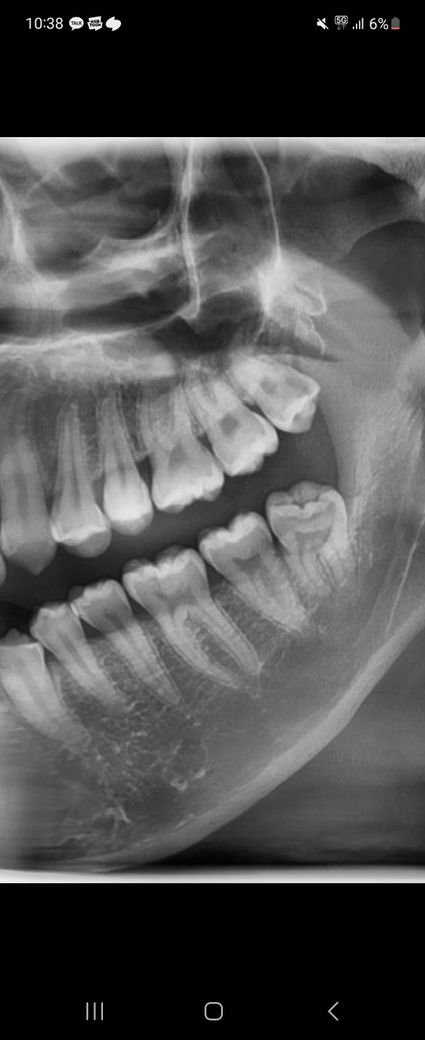

위쪽 사랑니인데 다음주 발치예정인데 오늘 갑자기 너무 아프네요...

찬물이 닿으면 시린데 그냥 시린게 아니라 심하게 찌릿하게 시려요..

겉으로 봤을땐 모르겠는데 충치가 많이 심한건가요?

왼쪽 위 사랑니의 경우 충치가 있는 상태입니다

아마 충치가 신경까지 영향을 준 경우 그런 느낌을 받을 수 있습니다